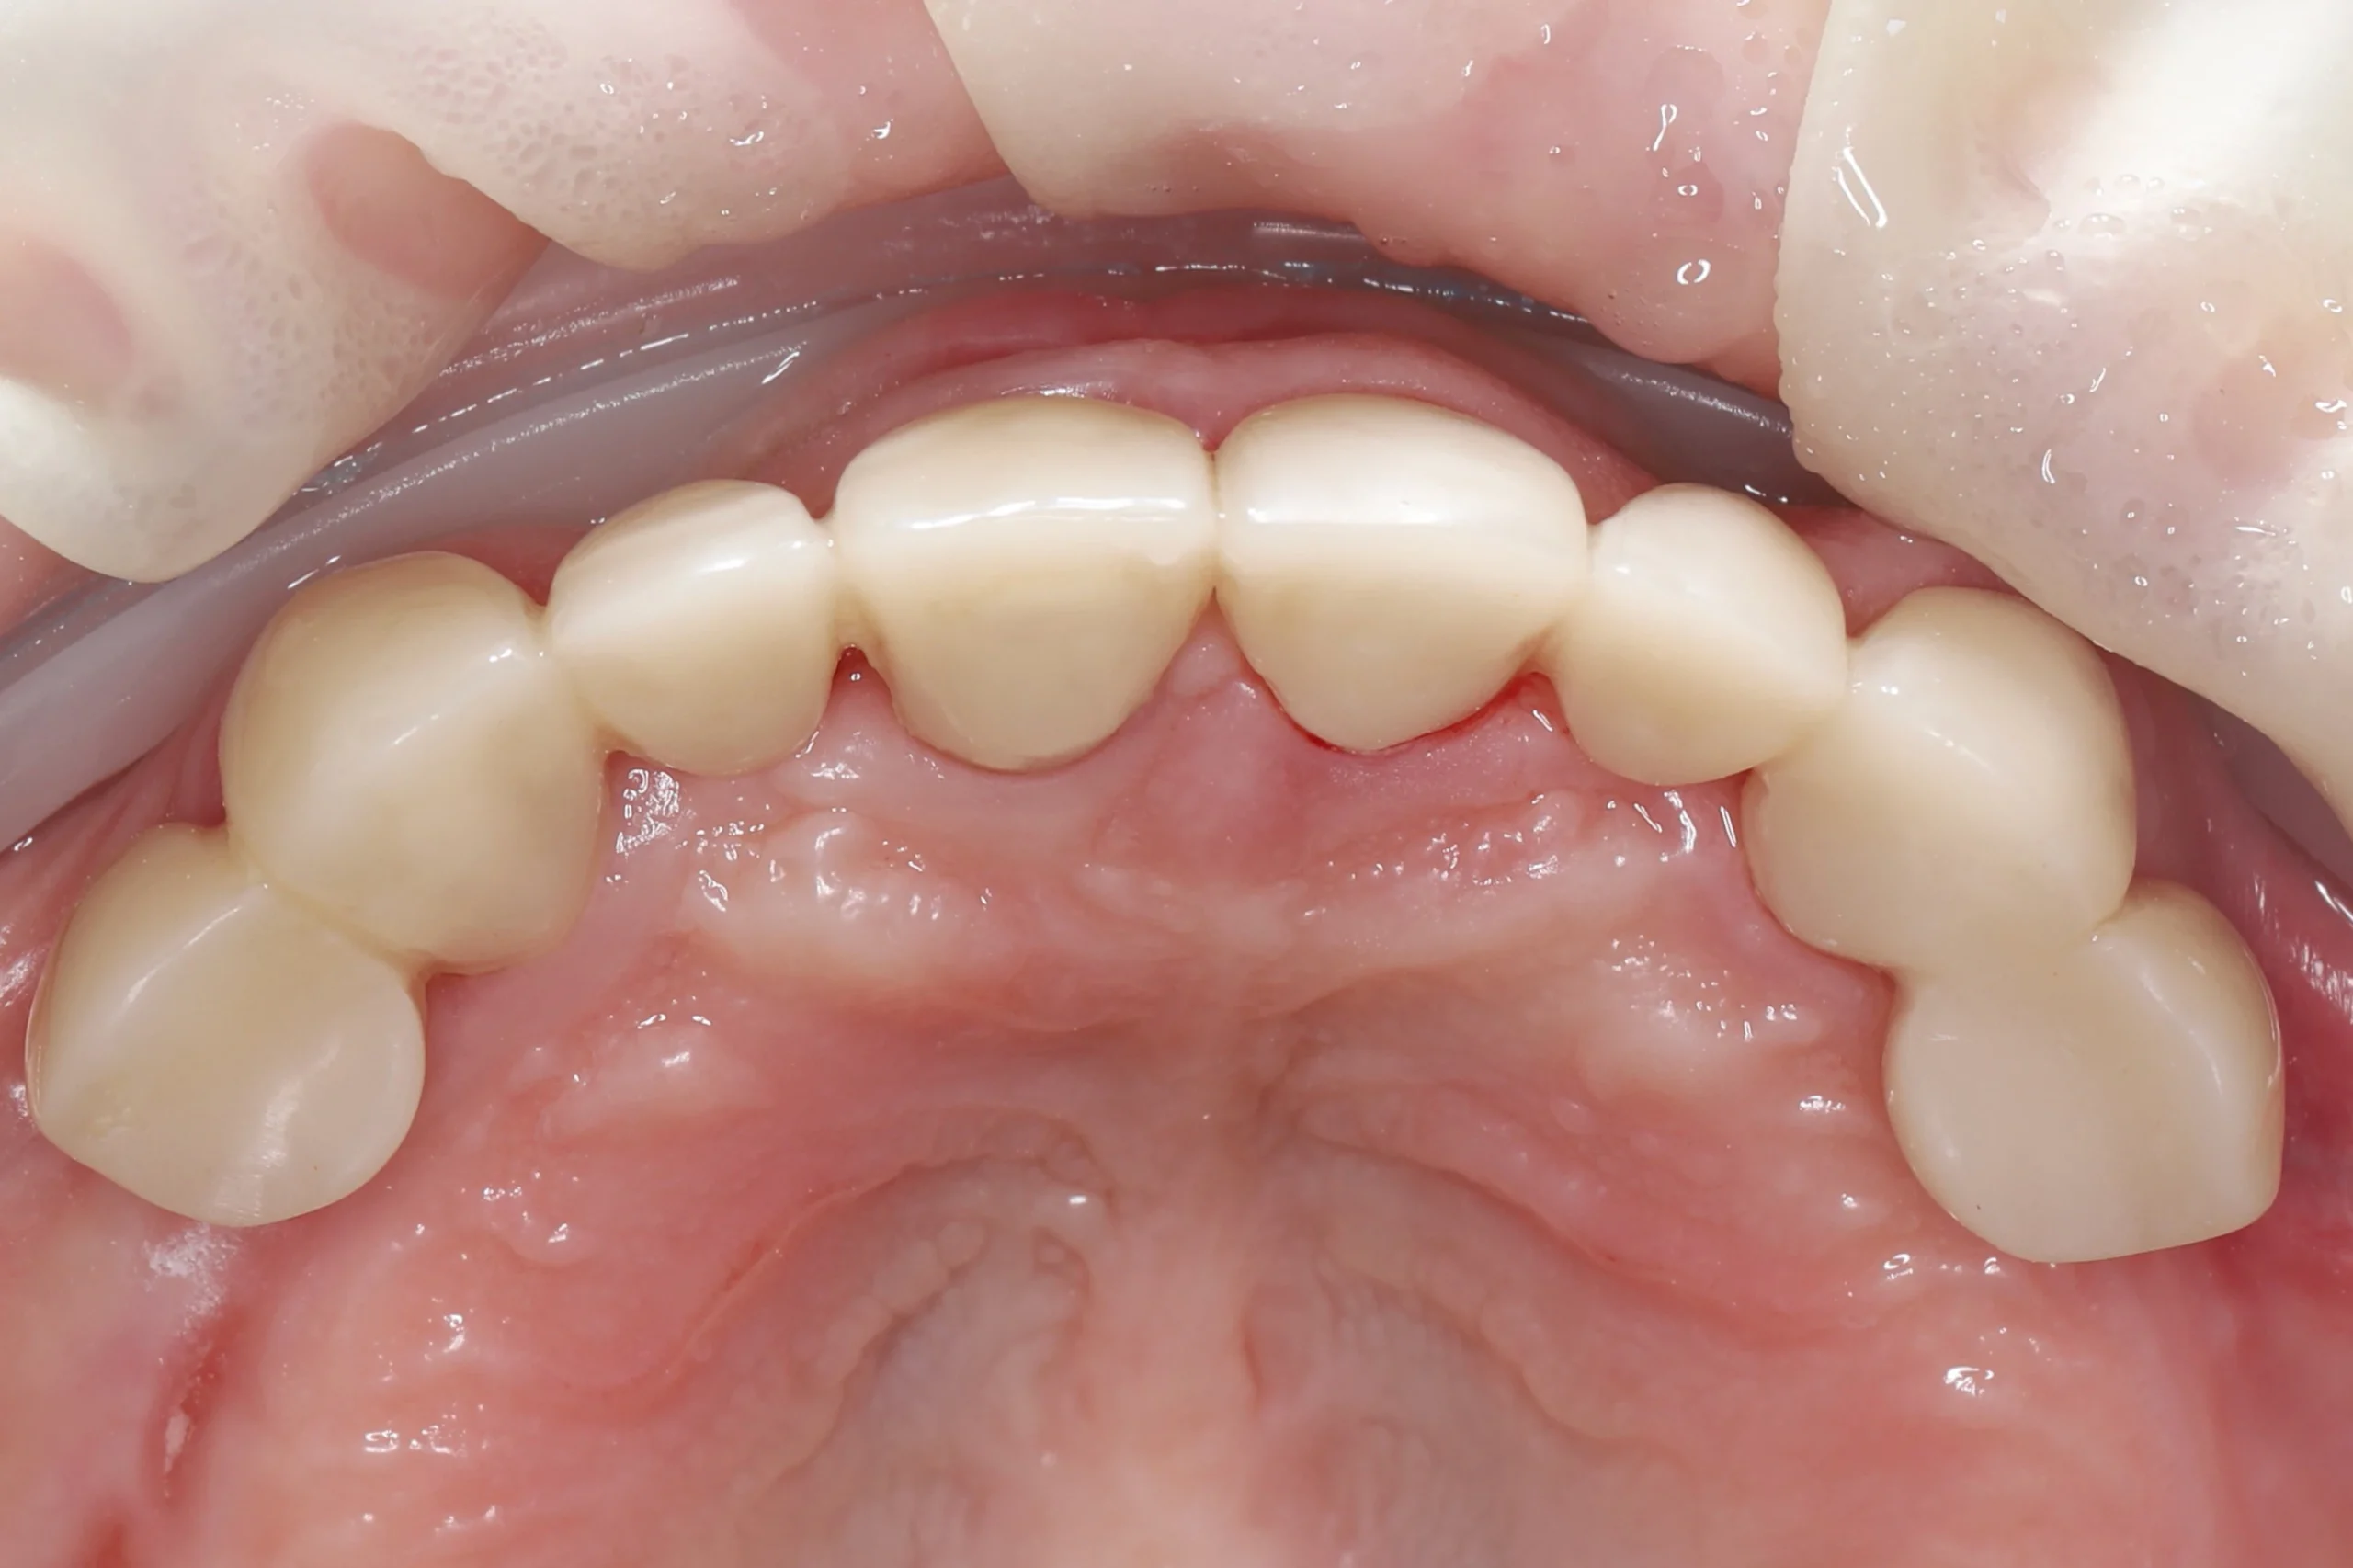

Фиксация PMMA

На основе цифровых оттисков в лаборатории изготовили PMMA-коронки (промежуточные между временными клиническими и постоянными). Они обеспечили стабилизацию прикуса, восстановление и адаптацию слизистой полости рта перед имплантацией.

Открытый кюретаж

Также с целью улучшения состояния дёсен, уменьшения глубины пародонтальных карманов и выраженности воспаления пациентке выполнили открытый кюретаж. В результате сформировался стабильный контур дёсен: они стали бледно-розовыми, плотными, без кровоточивости. Исчез галитоз — неприятный запах изо рта.

Текущий статус

Пациентка ходит с PMMA-коронками, окклюзия стабильна, слизистая без признаков воспаления. Через 3–4 месяца после имплантации планируется финальный этап — протезирование постоянными конструкциями.